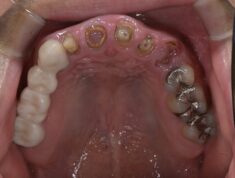

私達が目指すのは「二度と悪くならない治療」です。虫歯や歯周病を繰り返さない。歯がボロボロになってしまった方でも「噛める」だけでなく生涯健康を維持できる。子供の頃から生涯歯に困らない歯列をつくる。前時代的な歯科治療を脱して最新技術を用い、本質的な健康の実現を目指します。

最適な噛み合わせの実現で生涯歯の悩みから解放される、米国式の「OBI治療」を受けられる医院です。難易度の高い技術のため世界的に習得者が少なく、院長の菊地は日本全国の歯科医師に指導もしています。1本の虫歯から全顎症例、小児矯正まで最先端の噛み合わせ技術を駆使して長期的に歯を守ります。→詳しくはこちら

一般的な歯周病治療は歯茎の奥までグリグリと器具(刃物)を入れ、血を流し、歯を傷つけながら処置をします。実は、歯科先進国ではこの方法は時代遅れです。既に欧米では痛くなく、歯を傷つけず歯周病を治癒しています。当院ではこの北欧式の痛くない、安全な歯周病治療・予防を行っています。→詳しくはこちら

口腔内の状態に加え、顎の骨や筋肉の動きを総合的に判断し、最適な噛み合わせの位置を探しています。当院では、アメリカのOBI(Occlusion-Based Indicator)という噛み合わせ専門のアプローチを採用しています。院長は世界に約200人しかいないOBI治療医の一人です。矯正・インプラントの失敗やホワイトニングの戻りは、多くの場合、噛み合わせが原因です。

当院では北欧式の歯周治療・予防システムを導入しています。噛み合わせが悪いとプラークの蓄積や炎症が悪化し、予防や治療が難しくなるため、まず噛み合わせを治療することが重要です。